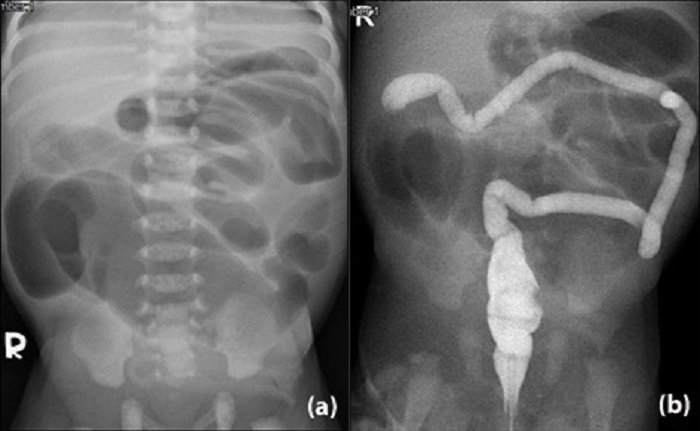

A full-term male baby weighing 3006 gm. was born of a 27-year-old mother who had a history of Hepatitis B and Chlamydial trachomatis infections. There were no antenatal visits. Breastfeeding was started soon after birth, however, he developed abdominal distension and bilious vomiting. His first stool (at day 1 of life) was a minimal whitish plug rather than meconium. Clinically, the baby was active and non-septic. The abdomen was distended with visible bowel loops. It was not tense nor discolored. The anus was at a normal position. A plain abdominal radiograph showed dilated bowel loops, absence of rectal gas, and no pneumoperitoneum (Fig. 1a). Contrast enema showed features of microcolon, but the contrast was unable to pass beyond hepatic flexure (Fig. 1b).

(a) Plain abdominal radiograph showed dilated loops of bowel, (b) microcolon up to hepatic flexure seen on contrast enema.